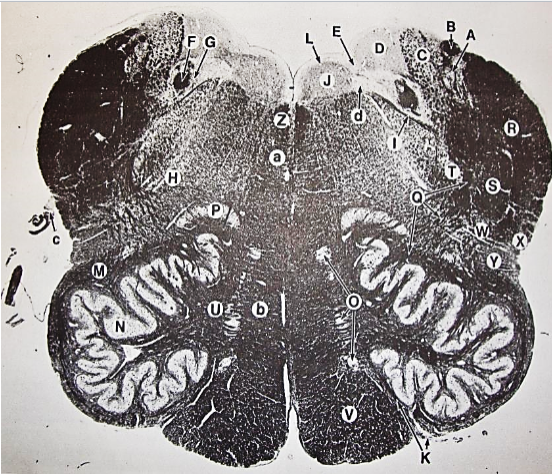

A

Fasciculus gracilis

B

gracile nucleus

C

fasciculus cuneatus

D

cuneate nucleus

E

spinal trigeminal tract

F+G collectively

spinal trigeminal nucleus

H

accessory nucleus

I

pyramidal decussation

J

rubrospinal tract

K

posterior spinocerebellar tract

L

anterior spinocerebellar tract

M

lateral spinothalamic tract

N

anterior spinothalamic tract

O

lateral vestibulospinal tract

P

medial longitudinal fasciculus

Q

tectospinal tract